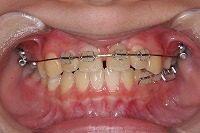

10歳4か月 | 10歳10か月 | 11歳1か月 | 11歳3ヵ月 | 11歳4か月 | 11歳7か月 | 11歳8か月 | |

反対咬合と前歯が生えてこない事を主訴に来院された、10歳4か月の男の子です。診断「下顎骨の過成長による骨格性反対咬合で上顎正中の左方偏位と埋伏歯を伴う」1期治療で反対咬合の解消と埋まっていた前歯を牽引しました。